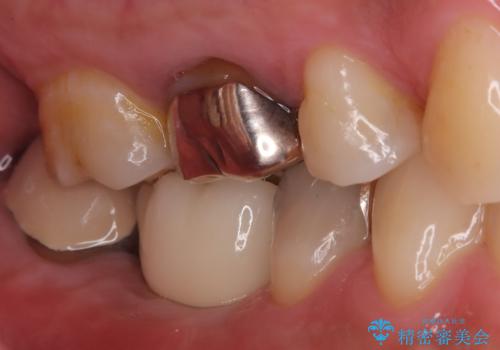

【インプラント】食事中に歯が割れた! かなり深いところまで歯が割れていた

- 「硬い物を食べたら歯が割れた」を主訴に来院された患者さんです。

根っこのところまで歯が割れていたため、歯を残すことは不可能と診断し抜歯後、インプラントで治療を行いました。

破折の深さが歯根まで及んでいたため抜歯を行いました。